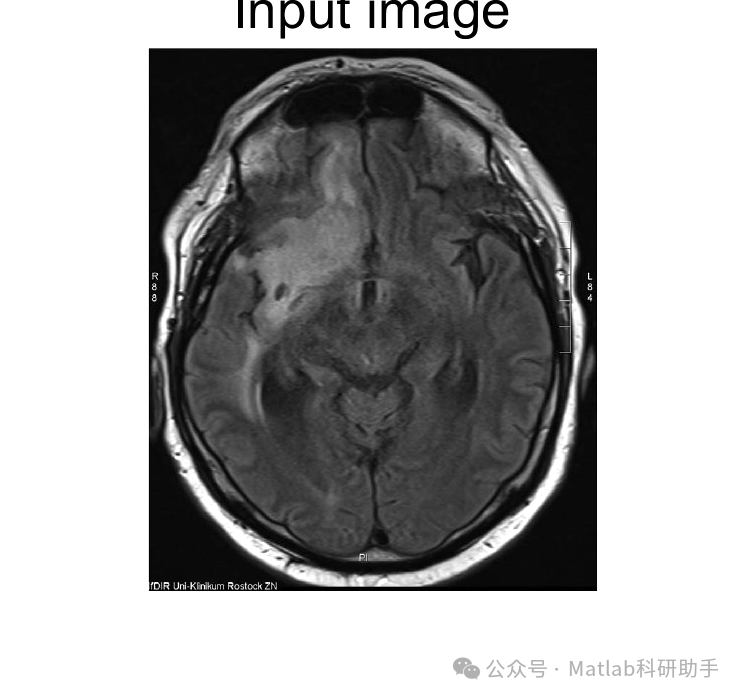

脑肿瘤是严重威胁人类健康的疾病之一,其早期、准确的检测和精确分割对于制定有效的治疗方案和提高患者生存率至关重要。近年来,随着医学影像技术的飞速发展,特别是磁共振成像(MRI)技术的进步,为脑肿瘤的检测和分割提供了强有力的支持。本文将深入探讨使用 MRI 图像进行脑肿瘤检测和分割的关键技术、挑战以及未来发展方向。

⛳️ 运行结果